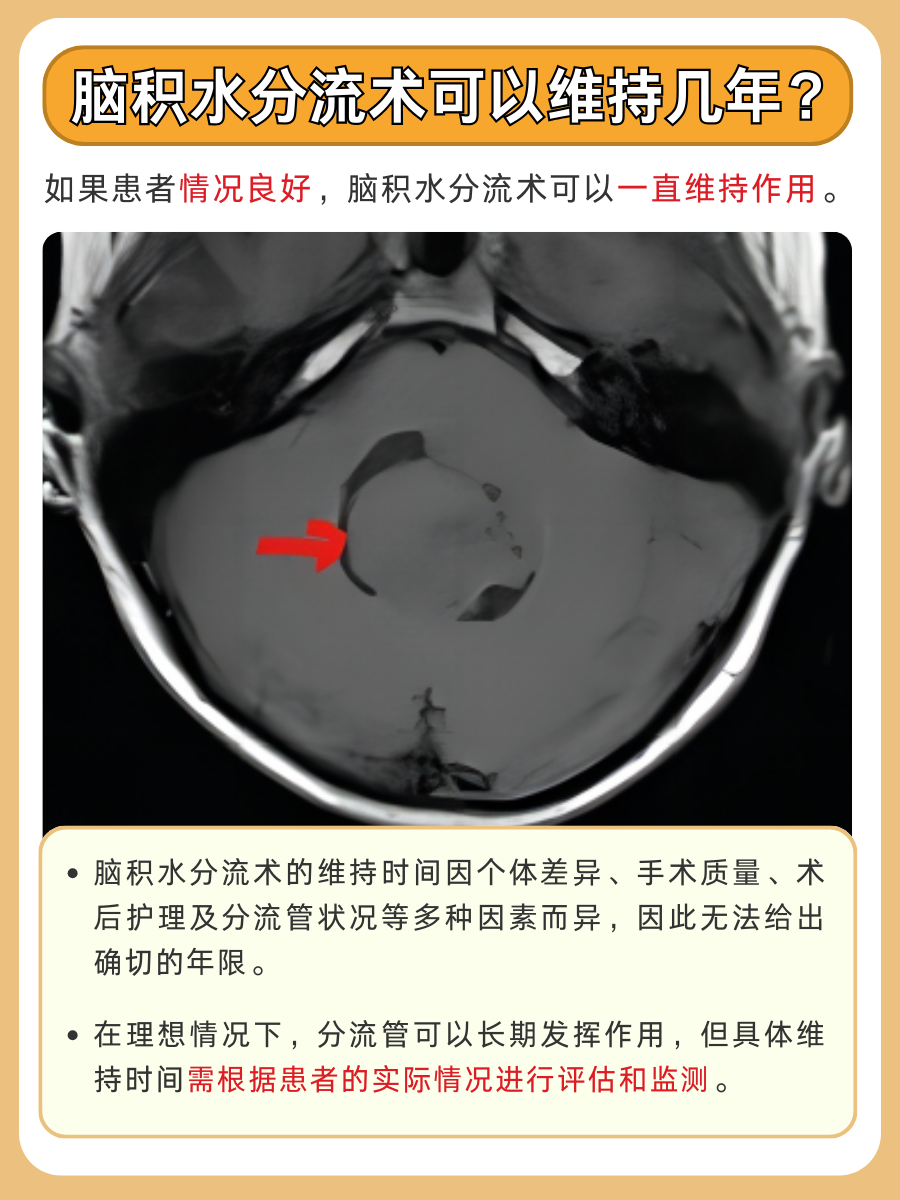

脑积水分流术的维持时间因个体差异而异,一般来说如果手术成功且术后未出现并发症,分流管可以长期发挥作用,甚至可能伴随患者终生。然而,需要注意的是,分流管可能会因各种原因(如感染、堵塞等)而失效,此时需要重新进行手术更换分流管。

1️⃣患者体质:患者的身体状况和免疫力对手术效果有重要影响。体质较好的患者,术后恢复更快,分流管的维持时间也相对较长。

2️⃣手术质量:手术操作的质量直接影响分流管的放置位置和引流效果。高质量的手术可以确保分流管长期稳定运行。

3️⃣术后护理:术后护理对于手术效果的维持至关重要。患者需要遵循医嘱,按时进行复查和护理,以减少并发症的发生。